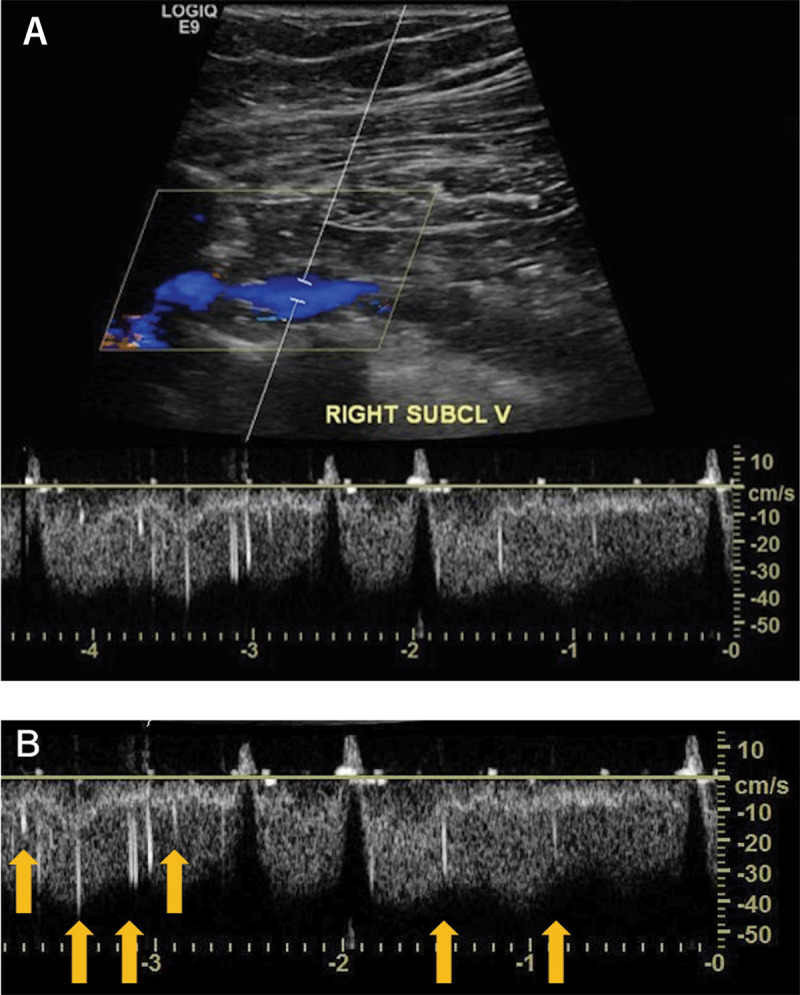

Fat emboli may occur in patients after traumatic fractures or orthopedic procedures; however, their clinical detection is a very rare finding. Here, we describe a 77-year-old female who was admitted to the emergency department with a fracture of the right humerus. We diagnosed fat embolism after an ultrasound of the right subclavian vein. The embolism was detected by high-intensity transient signals present on the spectral Doppler. While these signals are well known for microembolization in transcranial Doppler, to our knowledge this is the first case report in the medical literature to observe and describe high-intensity transient signals seen in the upper extremities by spectral Doppler. Although it is unusual to detect a fat embolism in transit, we believe clinicians should be aware of this finding, particularly when evaluating high-risk patients.